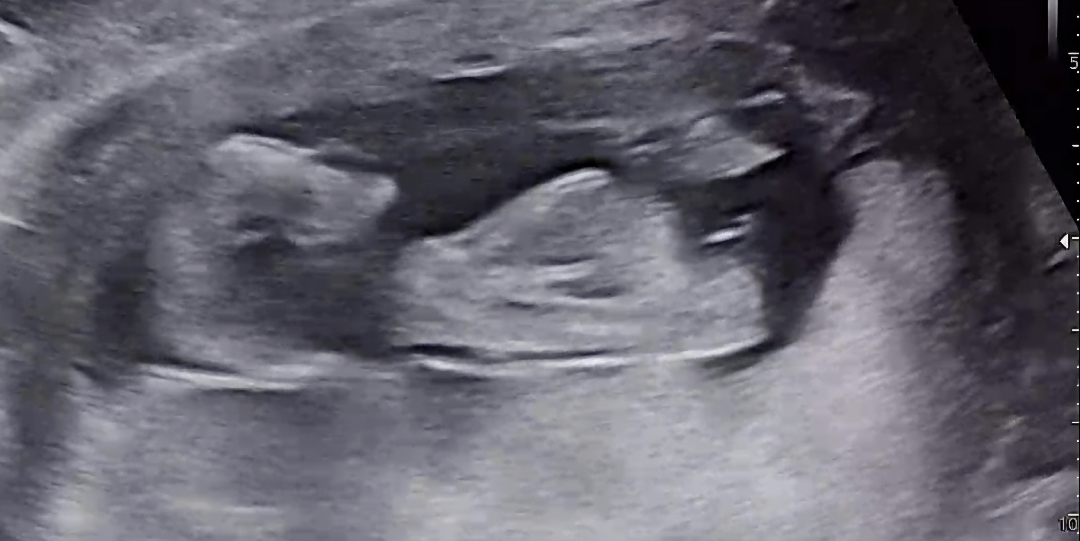

각도법 봐주세요!!

각도법한번봐주세요!!